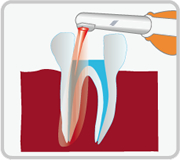

根管治療とは、リーマーやファイルと呼ばれる器具で細菌に感染してしまった歯質や神経を徹底的に除去し、歯の根の病気(根尖病変)を治療・予防するものです。虫歯が歯髄まで進行(C3以上)した場合や、根の病気になってしまった場合、根管内の神経を取り除く必要があります。神経を取った後、根管内を消毒し、薬を詰めて細菌が入り込まないようにします。

根管治療は歯科治療の基礎となる重要なものです。適切な根管治療がされていない歯に例えば高価なセラミックスクラウンを入れても、後々根の中に膿がたまってきたり、炎症が起こったりして、せっかく装着したセラミックスクラウンを外して再治療が必要となることが大いにありえます。最悪の場合、抜歯というケースも考えられます。

そのような事態をさけるため、歯髄(歯の神経)を除去する際には、将来的に病変ができないように、また、すでに病変ができてしまっている歯であれば、その病変を治すために、丁寧な根管治療を行う必要があります。適切な根管治療はその歯の寿命を決定付ける、大切な治療なのです。

根管は完璧に清掃を行わなければ、「痛み」「腫れ」などの原因となったり、「根尖病巣」という病気になってしまう可能性があります。しかし、根管の構造は非常に複雑で、肉眼での治療ではその精度に限界があります。

根管は完璧に清掃を行わなければ、「痛み」「腫れ」などの原因となったり、「根尖病巣」という病気になってしまう可能性があります。しかし、根管の構造は非常に複雑で、肉眼での治療ではその精度に限界があります。